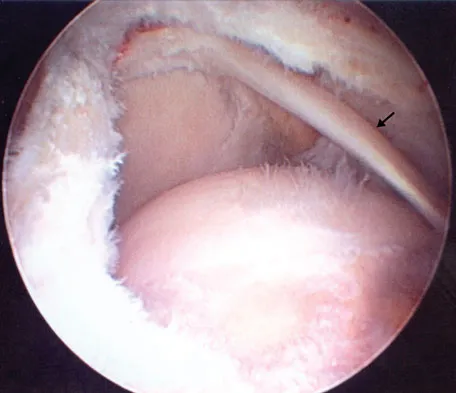

Figure 43 shows an arthroscopic view of a right shoulder through a lateral portal in the beach chair position. The arrow is pointing to what structure?

Explanation